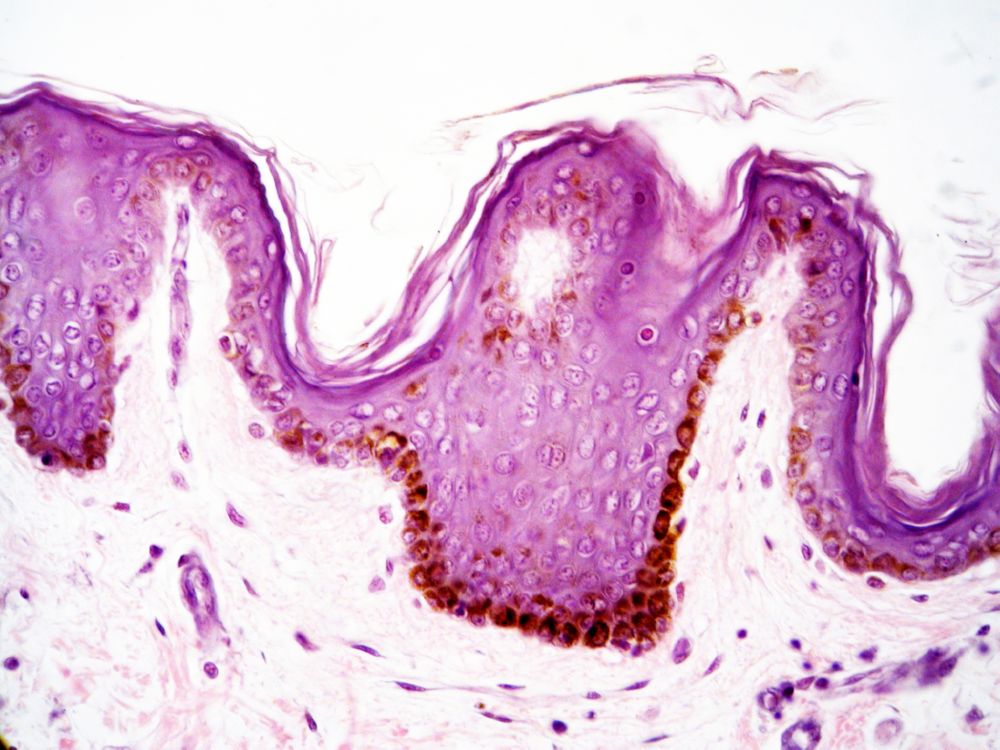

Verhornendes Epithel der Haut in HE-Färbung. Braun stechen die Pigmentgranula hervor, die nicht aus der Färbung stammen, sondern die Haut natürlicherweise braun gefärbt haben.